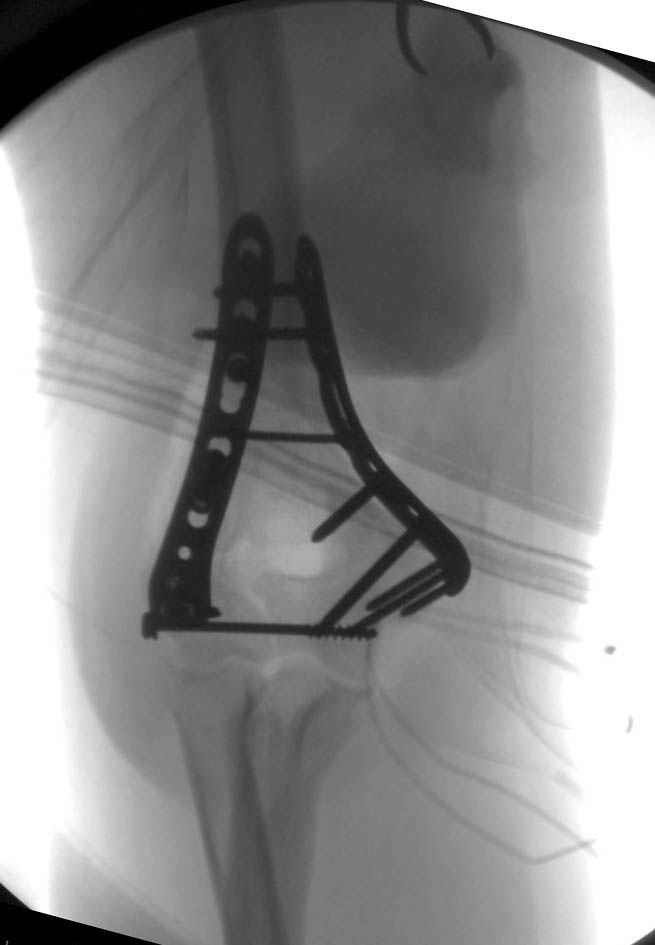

На шестой день сделали открытую репозицию чрезлоктевым доступом двумя locking plate, локтевой нерв был ушибленным, после операции положительная динамика в Flexor Carpi Ulnaris. Фиксацию локтевого отростка произвели tension band technique с дополнительным шурупом.

Этапы операции на снимках....